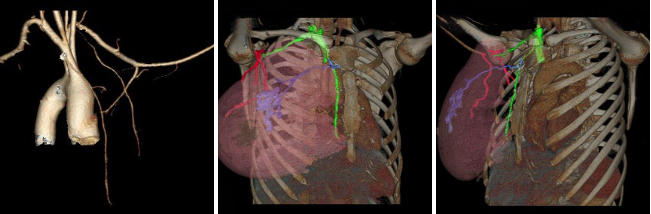

病例一 女,30歲, 行巨乳癥術(shù)前CT檢查。

綠色血管是鎖骨下動(dòng)脈和內(nèi)乳動(dòng)脈。 紫色的是從內(nèi)乳動(dòng)脈上面發(fā)出來(lái)的胸廓內(nèi)動(dòng)脈, 主 要是滋養(yǎng)乳腺的內(nèi)上象限。 紅色血管是從腋動(dòng)脈發(fā)出的胸廓外動(dòng)脈, 滋養(yǎng)乳房的外下象限。

病例二 女,28歲, 胸部塑型術(shù)后復(fù)查。

運(yùn)用640層寬體探測(cè)器CT設(shè)備小焦點(diǎn)、高清模式的超低劑量智能追蹤法及動(dòng)態(tài)灌注掃描方式,通過(guò)了解鎖骨下動(dòng)脈、胸廓外動(dòng)脈、胸廓內(nèi)動(dòng)脈、腹淺動(dòng)脈以及遠(yuǎn)端分支,和所支配的從淺表到深部組織的供 血,方便對(duì)巨乳癥、乳腺癌皮瓣移植術(shù)后及胸部塑形等患者的精準(zhǔn)手術(shù),保證末梢循環(huán)和皮膚組織的供血,減少遠(yuǎn)端末梢組織的壞死以及并發(fā)癥。給臨床醫(yī)生進(jìn)行手術(shù)入路指導(dǎo)。